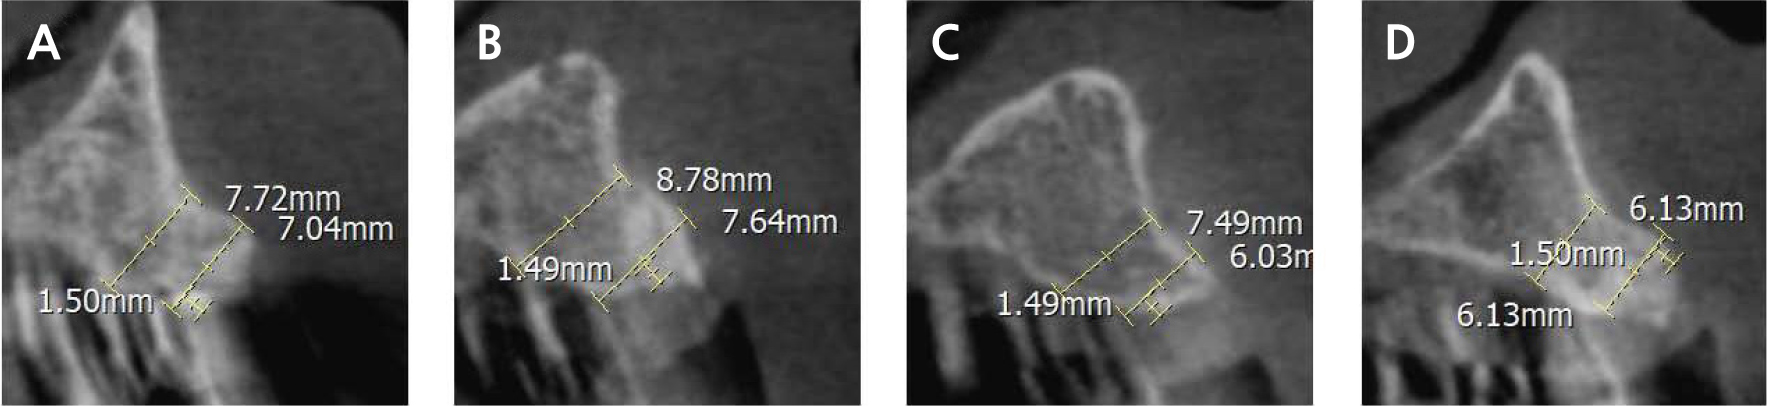

After 8 months of uneventful healing (Fig. 1H), cone-beam computed tomography (CBCT) confirmed that the bucco-palatal width was at least 6 mm (Fig. 2), allowing the placement of a 4 mm diameter implant. A full-thickness flap was raised in the anterior maxillary teeth region, and the bone was augmented under the healthy periosteal and soft tissues (Fig. 1I).

The bone regeneration area, along with the surrounding pristine bone, exhibited radiopacity on CBCT imaging. Furthermore, the regenerated bone area demonstrated hardness similar to that of the adjacent pristine bone. In addition, implant placement was feasible at #12–22 sites, as they exhibited adequate bucco-palatal widths (Fi. 2). However, caution was exercised to ensure the exclusion of the proximity to the nasopalatine canal in the case of #11 site and proximity to the tilted #23 implant in the case of #22 site.